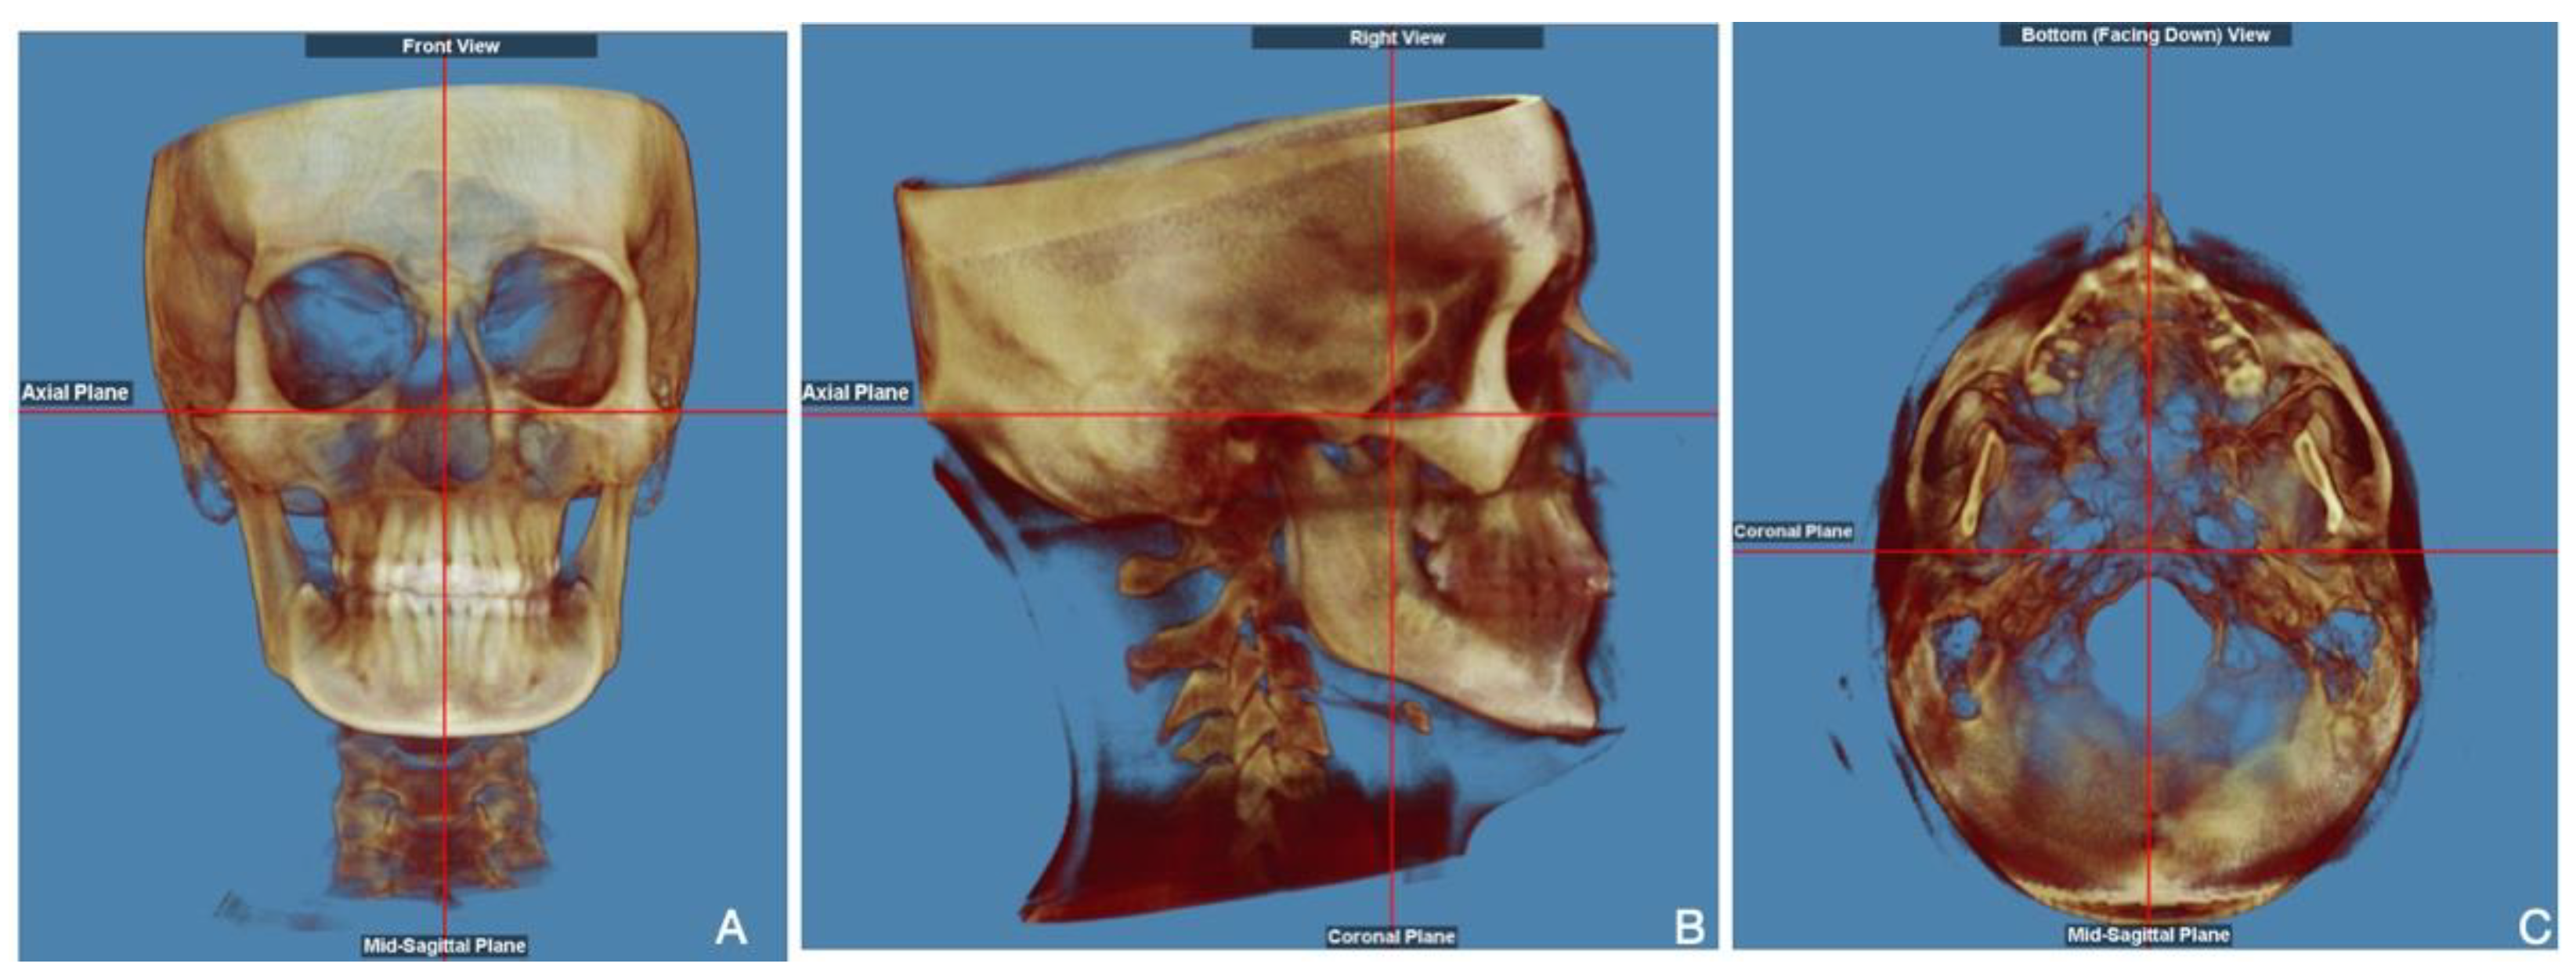

- Verma, S.K.; Maheshwari, S.; Gautam, S.N.; Prabhat, K.; Kumar, S. Natural head position: Key position for radiographic and photographic analysis and research of craniofacial complex. J. Oral Biol. Craniofac. Res. 2012, 2, 46–49. [Google Scholar] [CrossRef]

- Tian, K.; Li, Q.; Wang, X.; Liu, X.; Wang, X.; Li, Z. Reproducibility of natural head position in normal Chinese people. Am. J. Orthod. Dentofac. Orthop. 2015, 148, 503–510. [Google Scholar] [CrossRef]